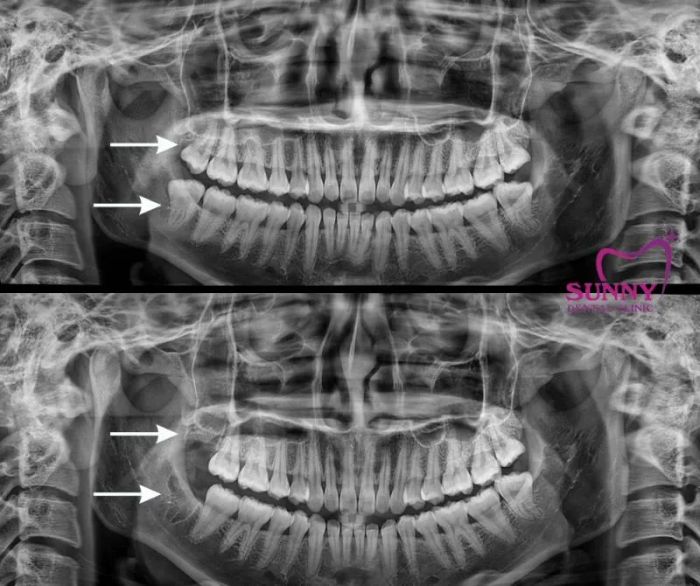

Wisdom tooth extraction process at Sunny Dental: Before the extraction, the dentist will take comprehensive X-rays and a CT scan of the bone to assess the nerve areas around the tooth. With the CT scan, the dentist can determine the direction of the tooth’s growth to make the extraction simpler and minimize impact on the surrounding bone. The clinic prepares a sterile environment to ensure no infections occur after the procedure.